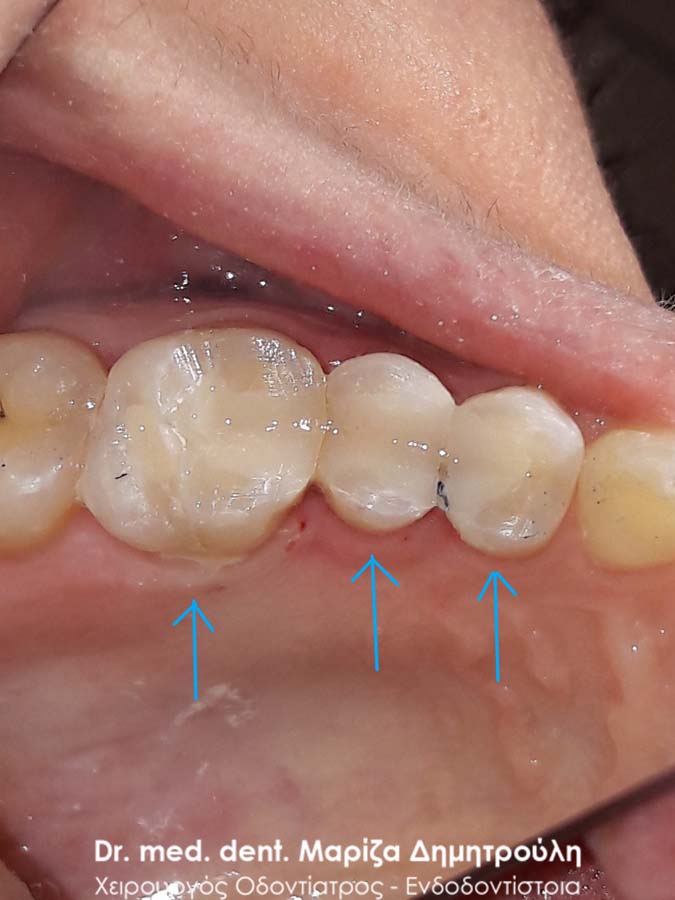

Αρχική εικόνα κάτω αριστερών γομφίων

Στο παρόν περιστατικό απουσιάζει η αρχική εικόνα των δύο δοντιών πριν αρχίσει ο εκτροχισμός τους. Διαθέσιμες είναι μόνο η ενδιάμεση εικόνα που παρουσιάζει το εύρος του οδοντικού ελλείμματος στα δύο γομφίους της αριστερής πλευράς της άνω γνάθου και η τελική εικόνα αποκατάστασης των δύο δοντιών.

Η ασθενής αισθανόταν τις τελευταίες μέρες έναν ήπιο πόνο κατά τη μάσηση τροφών. Μετά την κλινική εξέταση του στόματος διαπιστώθηκε η ύπαρξη τερηδονικών κοιλοτήτων στους δύο άνω αριστερούς γομφίους. Αποφασίστηκε με τη συναίνεση της ασθενούς η αντικατάσταση των σφραγισμάτων. Στον πρώτο γομφίο διορθώθηκε μόνο η μισή έκταση του παλιού σφραγίσματος, καθώς κρίθηκε οτι δεν ήταν απαραίτητη η αφαίρεση ολόκληρου του παλιού σφραγίσματος.